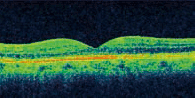

●光干渉断層計(OCT)

網膜の断層写真を撮影する検査です。

[健常]

写真の上方が眼球の内側、下方が外側です。

黄斑の中心(中心窩)は陥凹しています。